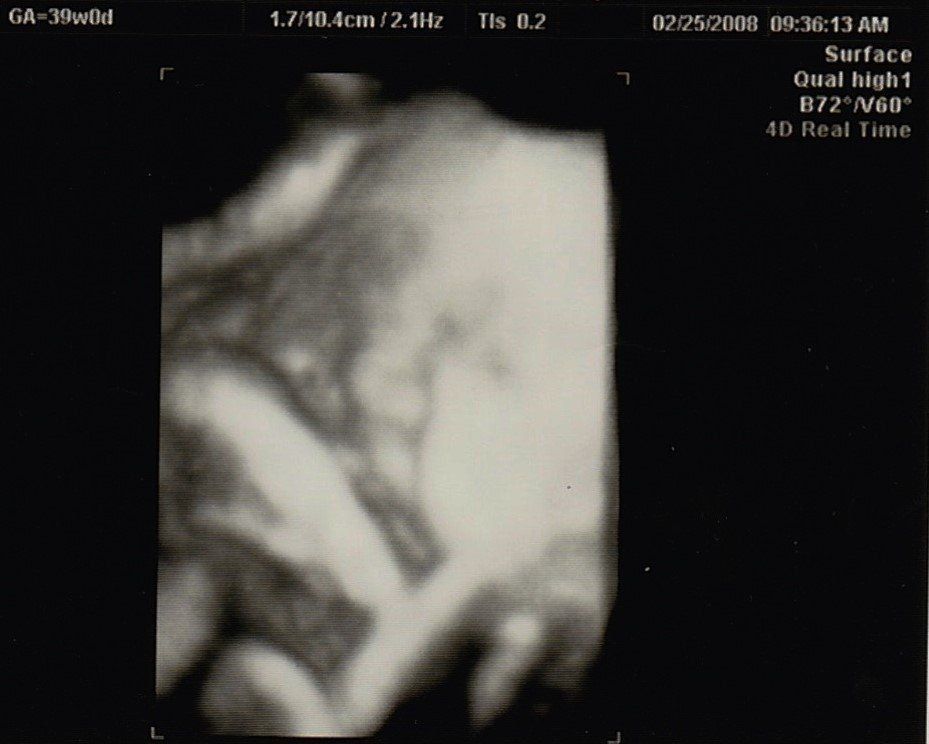

妊娠39週目のエコー写真

母や義母から「まだ生まれないの?」という電話と、たまたま出産予定日が日曜日で、夫、実父、義父も仕事が休み。その日に産まなきゃという義務感が生まれてきました。前日に自宅近くの坂道を上り下り、たっぷり散歩し、スクワットをした結果、無事、予定日当日に出産できました。